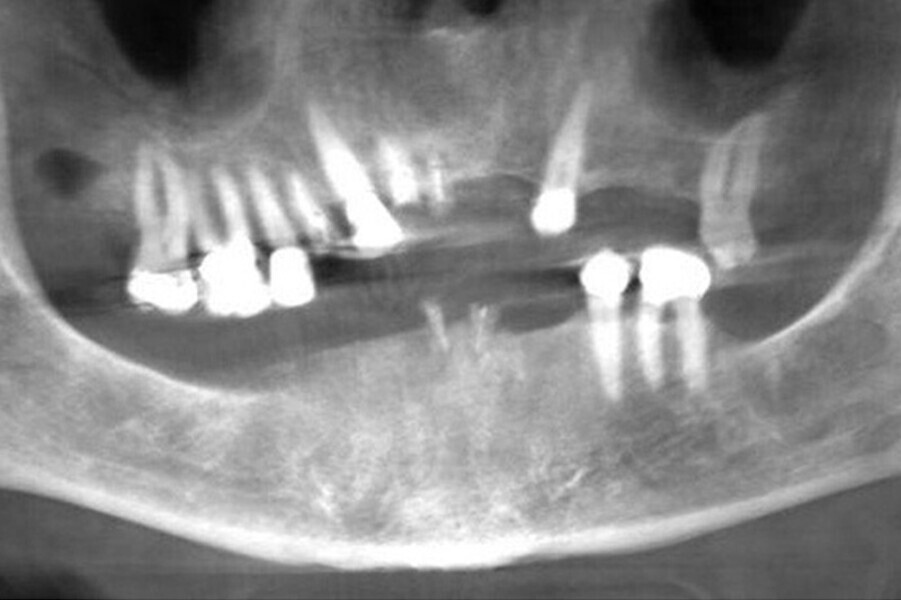

Fig. 7. Rx Pre-operatoria, Prótesis híbrida inmediata con 10 años de evolución y Rx Control a los 10 años.

Fig. 8. Rx Pre-operatoria, Prótesis híbrida inmediata con 10 años de evolución y Rx Control a los 10 años.